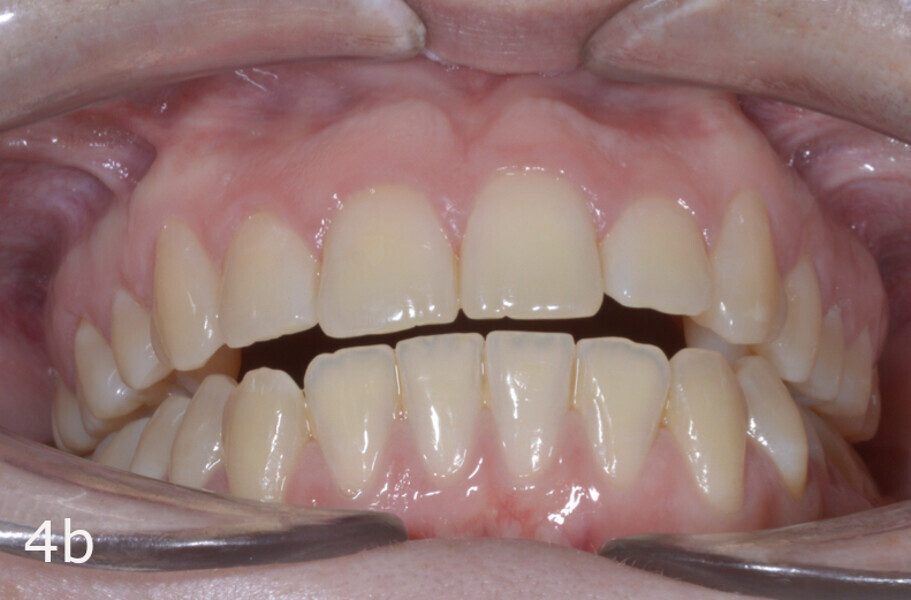

The 23-year-old dolichofacial female patient complained of not being able to chew properly. Facial examination showed a convex profile, an enlarged lower facial height, and a skeletal Class III malocclusion (Figs. 1–3). Intra-oral examination revealed an Angle Class III right subdivision malocclusion, anterior open bite, no overjet and a maxillary dental midline deviated about 3 mm to the right compared with the mandibular dental midline (Fig. 4). The panoramic radiograph confirmed previous extraction of the maxillary right first premolar and the presence of all four third molars (Figs. 5 & 6).

The treatment objectives included closing the anterior open bite, achieving a bilateral Angle Class I relationship and a proper overjet and overbite, correcting the midline discrepancies, and achieving a profile harmonisation. The treatment plan consisted of orthodontic camouflage treatment with asymmetric distalisation in three of the four quadrants using Invisalign aligners (Align Technology) and third molar extraction. The Invisalign Comprehensive package was chosen, and 63 pairs of aligners were used (Figs. 7–10). Each aligner was worn for 20 hours a day for one week each. The use of Class III elastics on both sides was indicated. Afterwards, ten refinement aligners were needed to improve the interdigitation on the right side (Figs. 11 & 12).